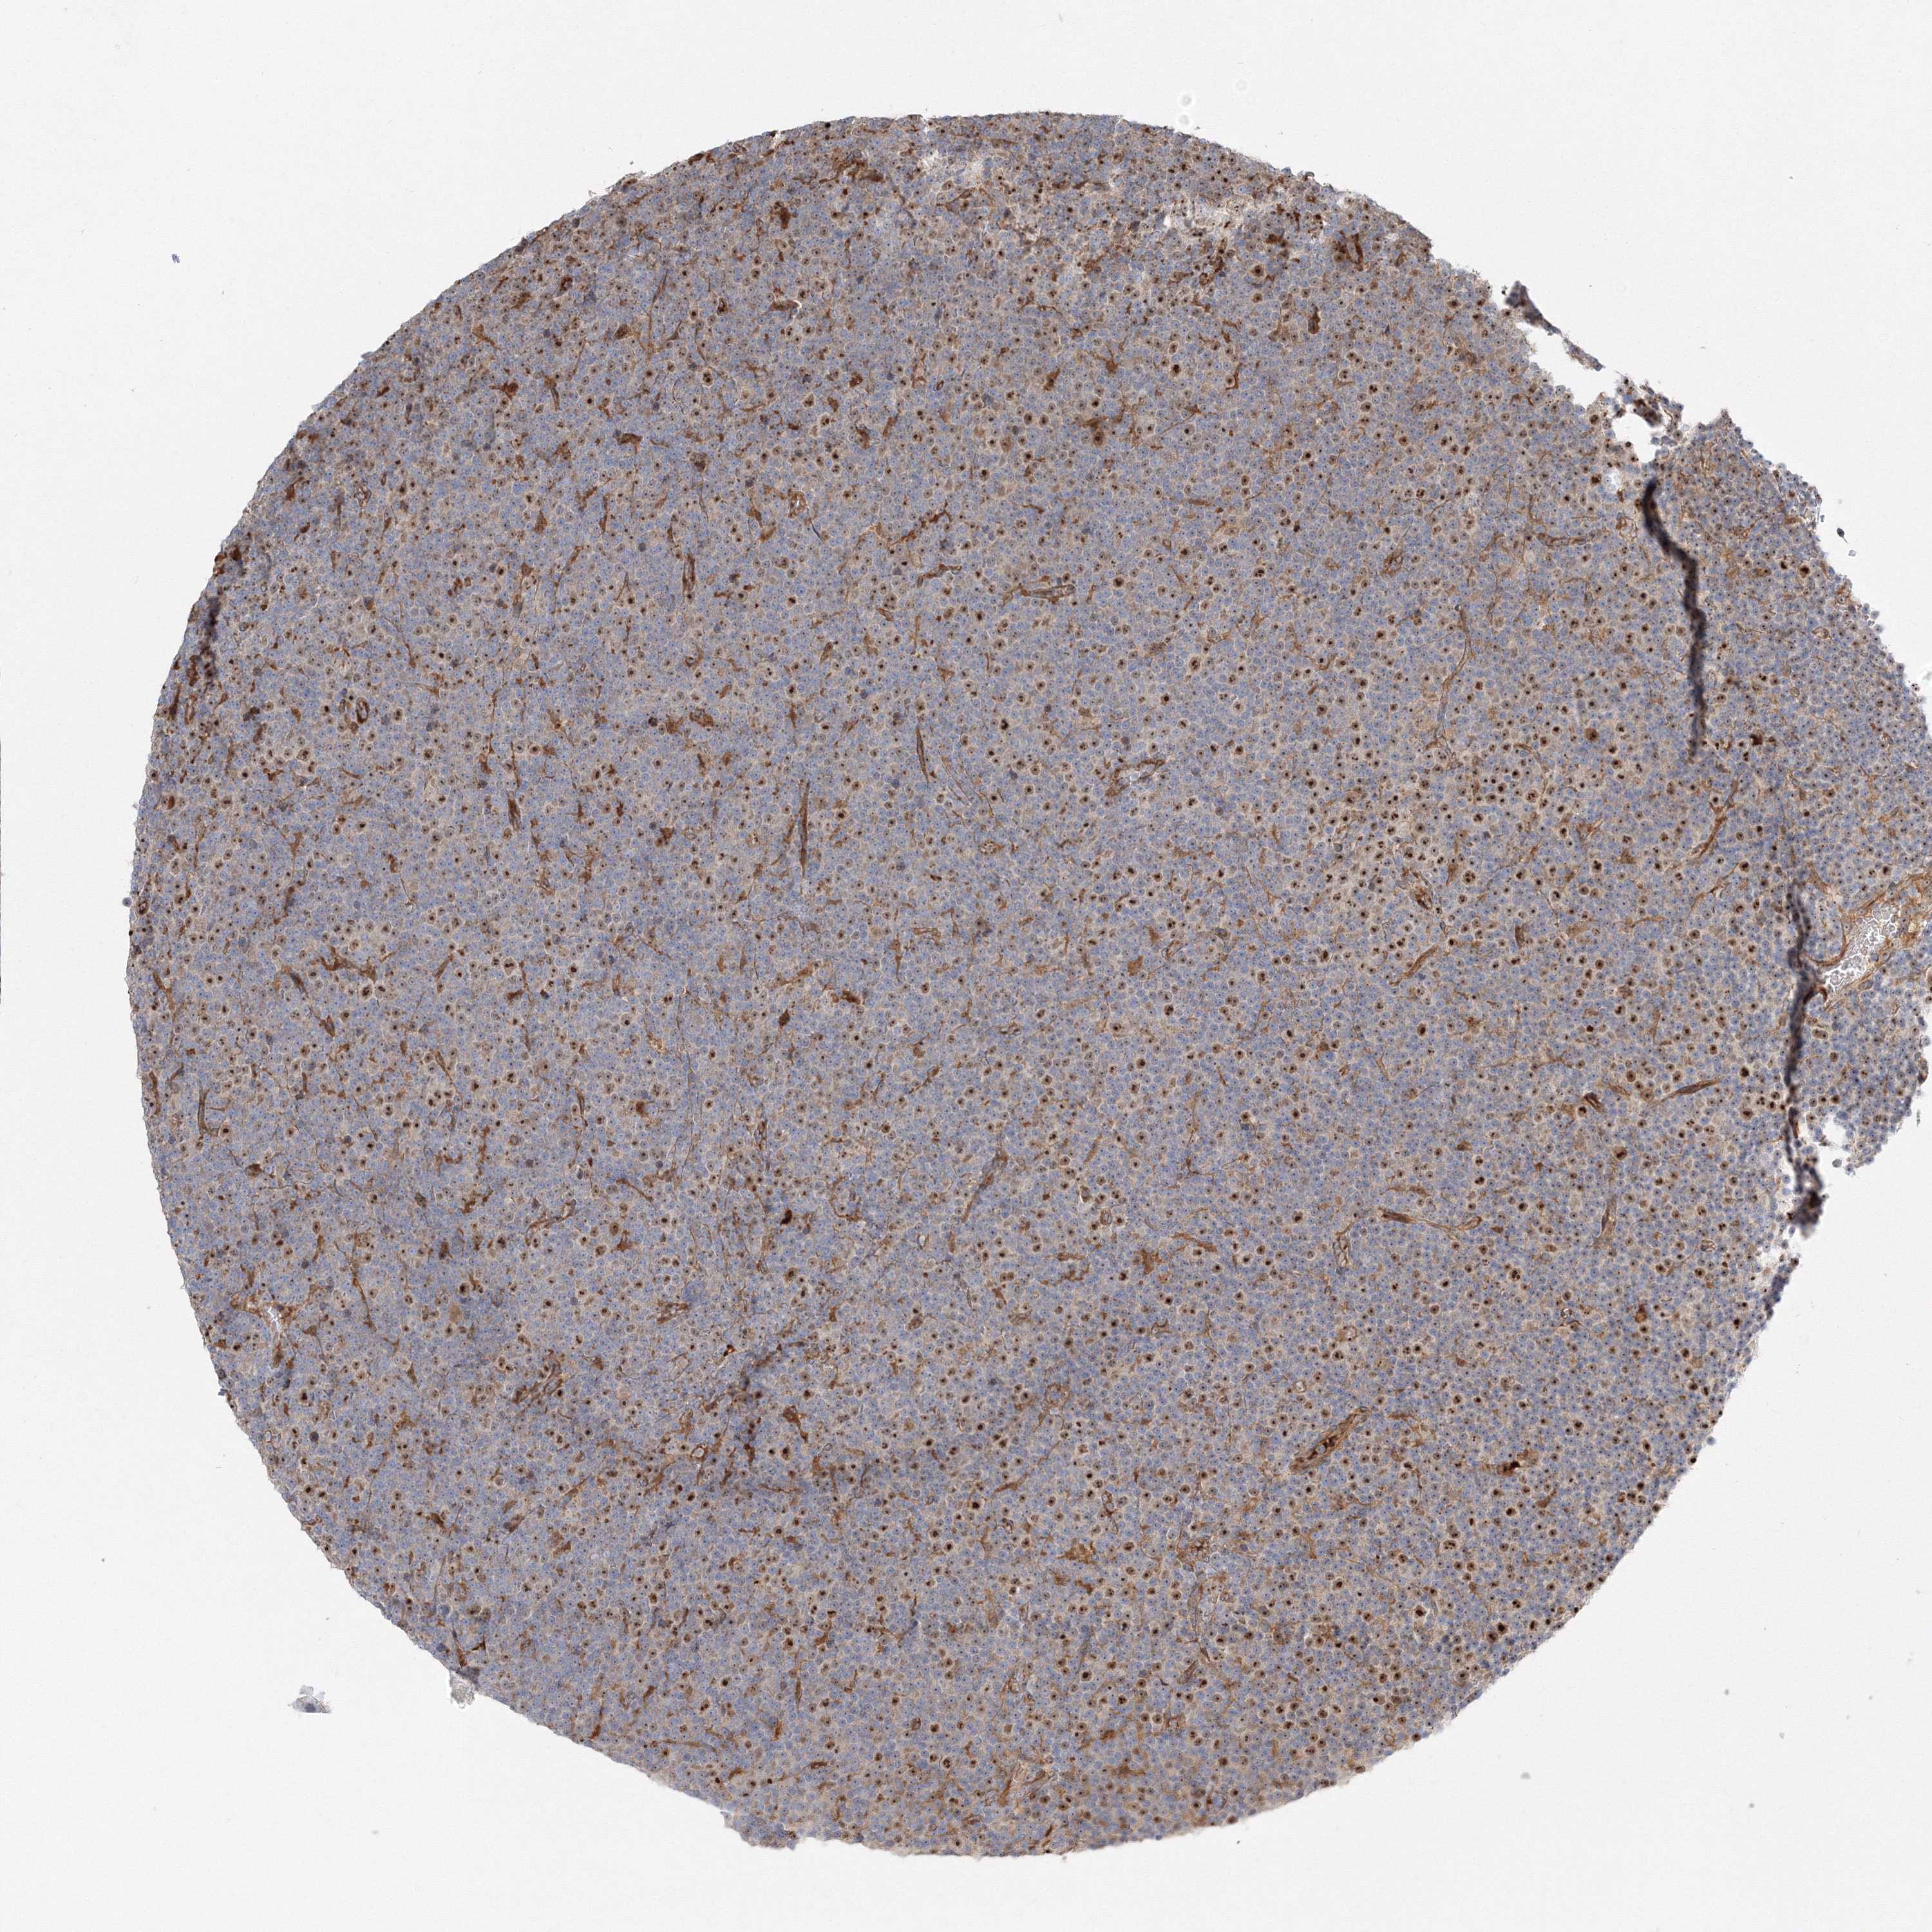

CANCER LYMPHOMA Show tissue menu

LYMPHOMA - Protein expressioni

A mouse-over function shows sample information and annotation data. Click on an image to view it in a full screen mode. Samples can be filtered based on level of antibody staining by selecting one or several of the following categories: high, medium, low and not detected. The assay and annotation is described here.

Antibody stainingi

Antibody staining in the annotated cell types in the current human tissue is reported as not detected, low, medium, or high, based on conventional immunohistochemistry profiling in selected tissues. This score is based on the combination of the staining intensity and fraction of stained cells.

Each image is clickable and will lead to virtual microscopy that enables deeper exploration of all samples and also displays staining intensity scores, fraction scores and subcellular localization as well as patient and tissue information for each sample.

Antibody HPA036295

Antibody HPA036296

Hodgkin's disease, NOS

Malignant lymphoma, non-Hodgkin's type, High grade

Malignant lymphoma, non-Hodgkin's type, Low grade